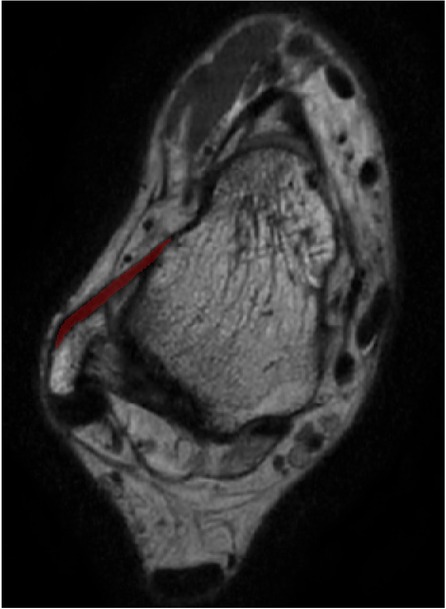

The ATFL's width and thickness in each model were measured on the fibula side, the middle side (halfway between insertion and origin), and the talus side, respectively (Figure 2). When measurements were taken using the 3D MPR data, we selected the middlemost axial layer of ATFL's footprint on the sagittal plane and the coronal plane. At this layer, the middle point of the footprint on the talus/fibula was selected as the measurement point. The distance between the two middle points was measured as the length. Similarly, the thickness was measured at three points on the same layer. Finally, the width was measured on the sagittal plane with homologous measuring sides. For the measurement on the 3D model, length was measured as the distance between the two middle points of the footprints on the talus side and the fibula side. The measurements of width and thickness were similar to the measurements on the 3D MPR images.

Figure 2. The measuring method on the 3D MPR image. The red line, blue line, and the green line indicate the measured spot on talar side, middle side, and fibular side, respectively.